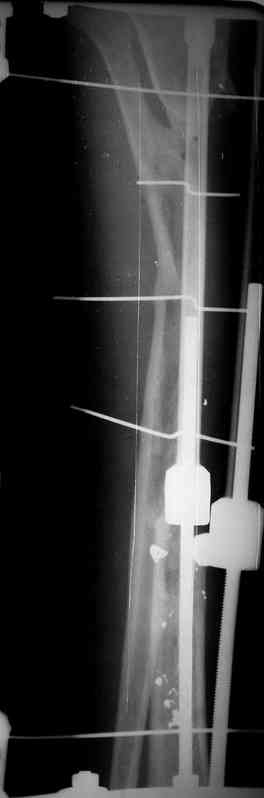

Я думал, что в нижнем отделе голени без мягкотканнего покрытия будет сложно проведения тибиализацию, но твой пример показывает - метод работает даже в таких трудных условиях.

Правда те мои случаи были сделаны давно, еще в Латинской Америке, и конечно качество исполнения отстает от идеалов, но, несмотря на отсутствие нормальных спиц с упором, метод сработал в свое время.

Приходилось встречать замещенные дефекты малоберцовой костью без применения метода Идизарова, и при соблюдении осторожности хрупкая малоберцовая за короткое время под вождействием нагрузки утолщались в диаметре.